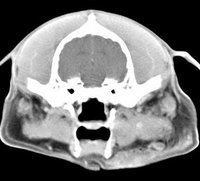

imágenes de TC en el perro | ||||||||||

ejemplo de imágenes de TC en el perro. Nótese la celulitis en la región parotídea izquierda | ||||||||||